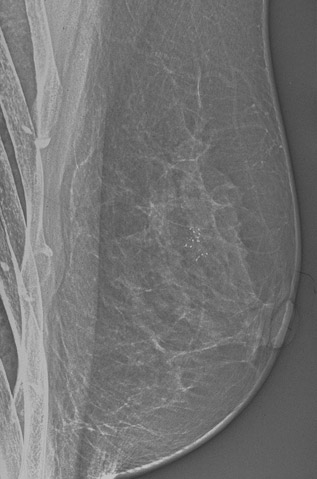

Click on the area of microcalcifications in the mammogram above:

This mammogram demonstrates a suspicious area with microcalcifications that could be a carcinoma or just an area of fibrocystic changes. On biopsy, this lesion had areas of fibrocystic changes with epithelial hyperplasia.